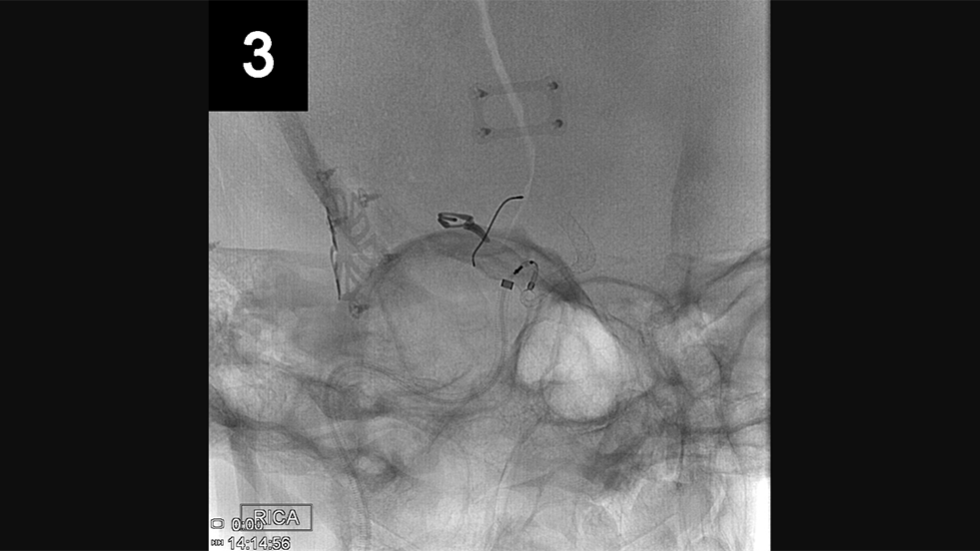

Endovascular Repair

Endovascular (from within the blood vessel) surgery, is performed through a catheter (a hollow, flexible tube) delivered from the groin or leg to the blood vessels in the brain. Thin platinum wires are pushed into the aneurysm, where they conform to the wall of the aneurysm forming a coil mass. Since blood clots form around the coils, the chances of a rupture are greatly reduced. Recovery time is typically only one to three days.

Primary Coil Embolization, Technique: Aneurysm

Primary Coil Embolization: Treats aneurysm from the inside rather than the outside. Fill aneurysm with embolic coils in order to obliterate blood flow.